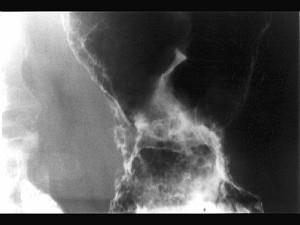

问题 男,65岁,中上腹痛半年,X线检查如图,最可能的诊断是 ( )

选项 A、胃间质瘤 B、糜烂性胃炎 C、胃溃疡 D、胃浸润癌 E、胃息肉

答案 D